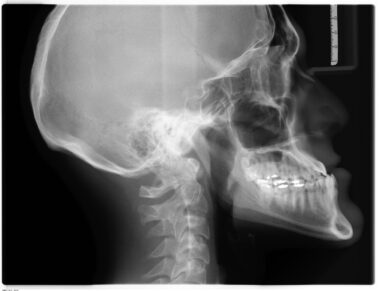

Understanding the types of fractures is key to formulating the most effective rehabilitation strategies. Fractures can be classified based on their severity, location, and overall complexity. Common types include simple, compound, and comminuted fractures. Each type requires a distinct approach to rehabilitation. For instance, compound fractures may necessitate more extensive surgical intervention before rehabilitation begins. Effective communication between the medical team and the patient ensures that a personalized recovery plan is developed. Additionally, education on the healing process is critical; patients should understand what to expect during each phase. Knowing when to expect pain, swelling, or discomfort can prepare individuals psychologically. Incorporating functional training routines is also crucial, specifically related to tasks of daily living. Utilizing assistive devices during recovery can enhance mobility while reducing strain on healing bones. Availability of multi-disciplinary support, including occupational therapy, can facilitate a smoother transition back to normal activities. The timeline for recovery varies widely, often stretching from weeks to months depending on the injury’s severity and the individual’s overall health. Constant monitoring and adjustments to the rehabilitation program ensure optimized healing and functionality.